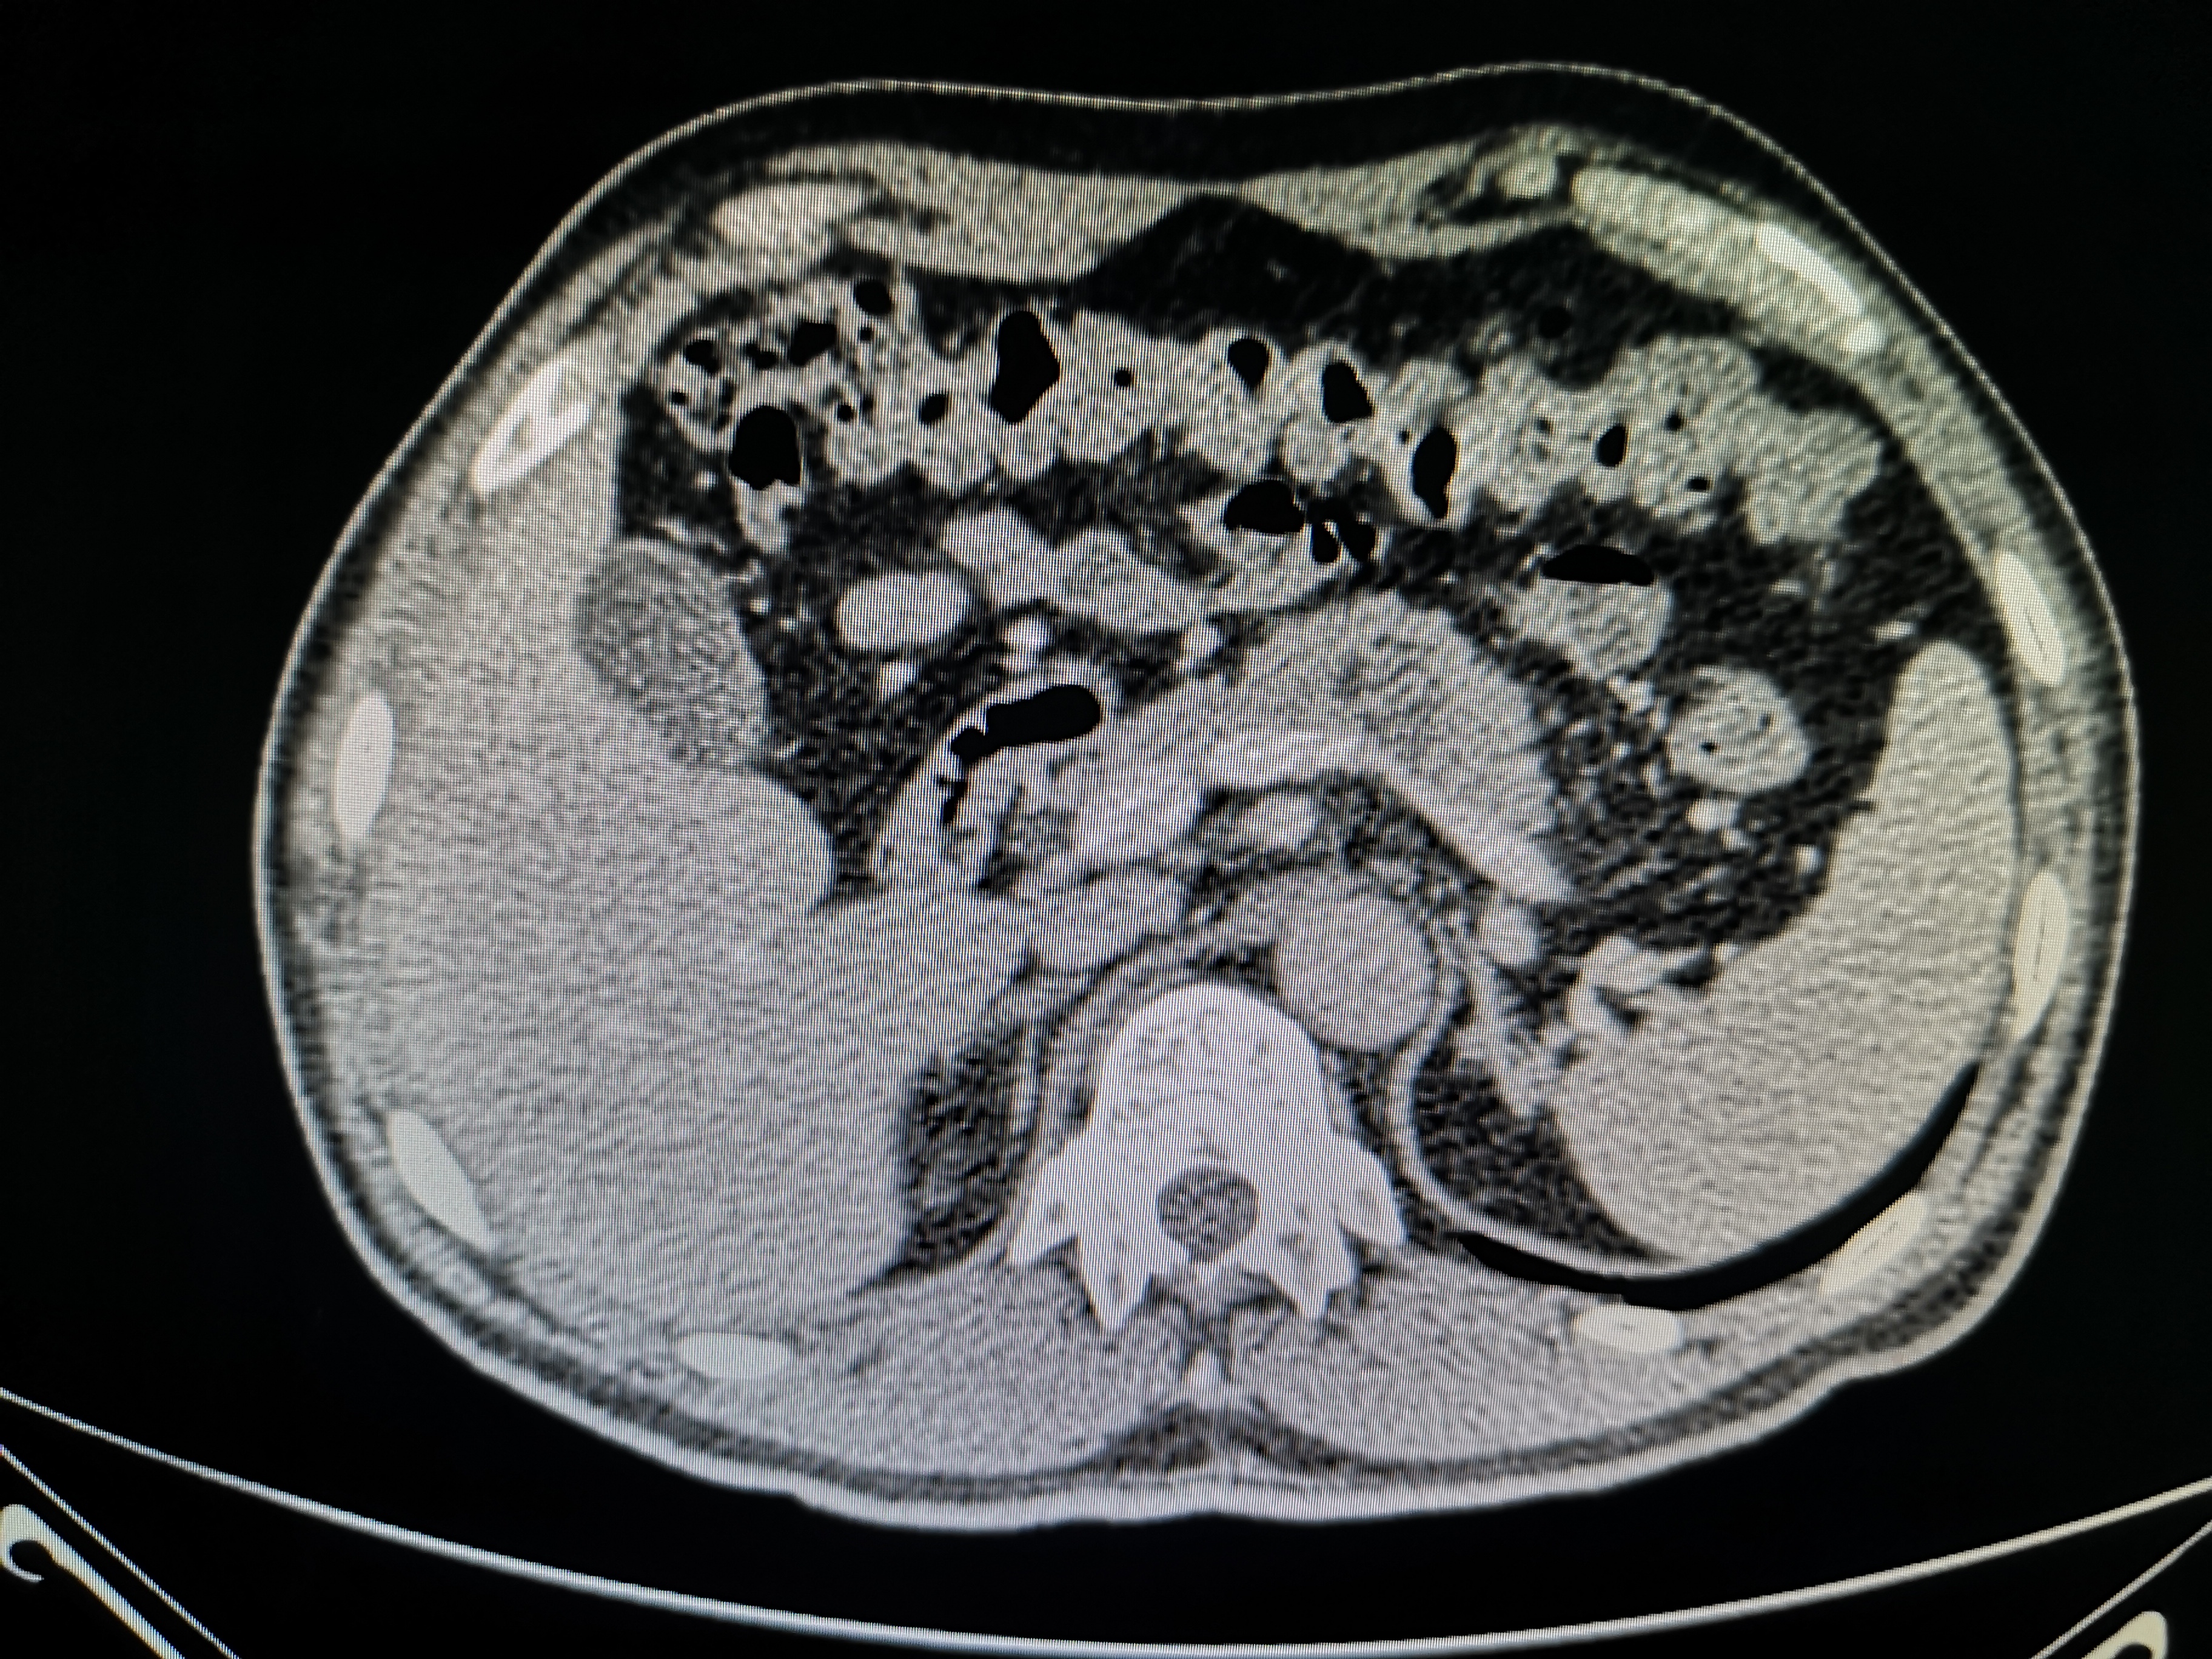

病例讨论-胰岛细胞瘤

图片尺寸960x720

ercp检查:腹部ct:胰头部富血供占位,胰岛细胞瘤?结合实验室检查.

图片尺寸419x324